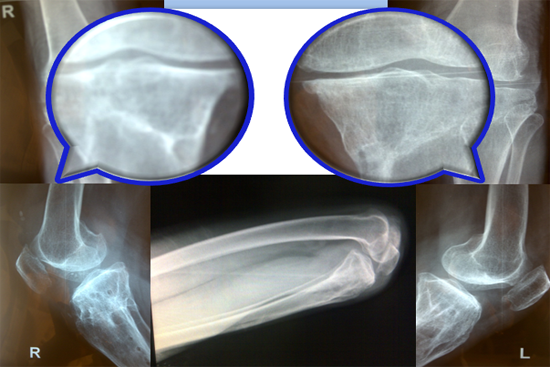

Knee Deformity